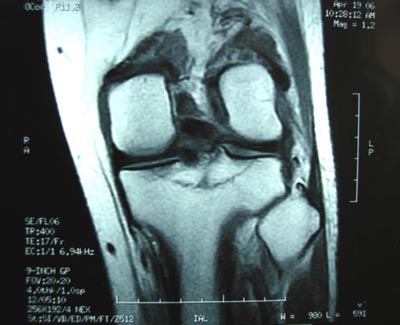

男,45。骑摩托车摔伤左膝肿痛三天,浮髌(+),活动受限。请大家看看片子有问题吗?

标题: 现将mri结果公布

手术证实是后交叉韧带胫骨附着处撕脱骨折。

术中用可吸收螺钉固定。